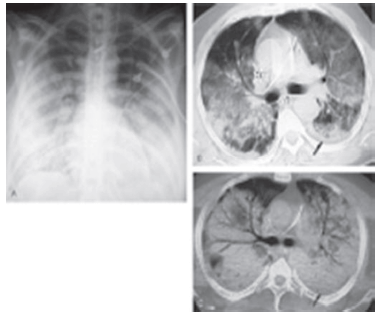

O conjunto de imagens abaixo representa o diagnóstico de: